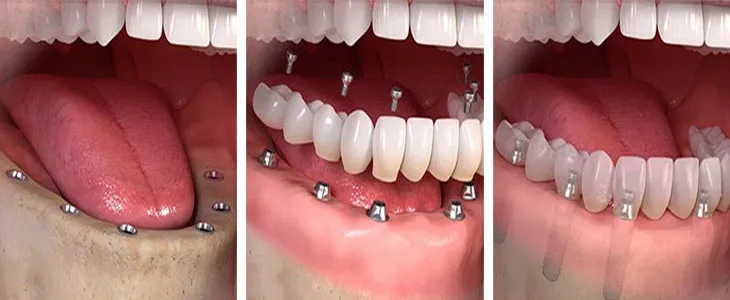

Tam dişsizlikte sabit protez seçeneklerinden biri olan All-on-Four yaklaşımının temel mantığını öğrenin.

Hiç Dişi Olmayana Kaç İmplant Gerekir?

Dental İmplant Cerrahisi: Kayıp Dişlerin Kalıcı ve Güvenilir Çözümü